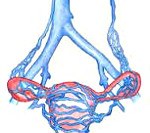

Варикозное расширение вен малого таза. Эктазия сосудов венозной системы малого таза, приводящая к нарушению кровооттока от внутренних и наружных половых органов. Проявляется видимым расширением промежностных и вульварных вен, сопровождающимся местным отеком, чувством тяжести и распирающих болей, кровотечениями. Характерны тазовые боли, дисменорея, диспареуния и тд симптомы. Варикозное расширение вен малого таза диагностируется посредством гинекологического осмотра и УЗИ с ЦДК, флебографии, КТ, лапароскопии. Лечение синдрома может быть консервативным (прием венотоников, ЛФК) или хирургическим (склерооблитерация/эмболизация гонадных вен, флебэктомия и тд ).

Варикозное расширение вен малого таза (ВРВМТ) - заболевание тазовых вен, связанное с нарушением их архитектоники и застоем венозной крови в малом тазу. В литературе варикозное расширение вен малого таза также обозначается терминами «синдром тазового венозного полнокровия», «варикоцеле у женщин», «синдром хронических тазовых болей». Распространенность варикозного расширения вен малого таза увеличивается пропорционально возрасту: от 19,4% у девушек младше 17 лет до 80% у женщин в перименопаузе. Наиболее часто патология тазовых вен диагностируется в репродуктивном периоде у пациенток в возрастной группе 25-45 лет. В подавляющем большинстве случаев (80%) варикозная трансформация затрагивает яичниковые вены и крайне редко (1%) наблюдается в венах широкой связки матки. Согласно современным медицинским подходам, лечение ВРВМТ должно осуществляться не столько с позиций гинекологии, но, прежде всего, с позиций флебологии.

Варикозное расширение вен малого таза может проявляться в двух формах: варикоза вен вульвы и промежности и синдрома венозного полнокровия. Более чем в половине случаев обе этих формы обусловливают и поддерживают течение друг друга. Изолированный вульварный и промежностный варикоз часто возникает в результате рефлюкса крови через сафенофеморальное соустье с поражением наружной половой вены и притока большой подкожной вены. Встречается у 30% беременных, после родов сохраняется у 2-10% женщин. Главным провоцирующим фактором варикоза вен промежности и вульвы служит давление растущей матки на подвздошную и нижнюю полую вены. Патоморфологической предпосылкой для варикозного расширения вен малого таза выступает рефлюкс крови по яичниковой вене.